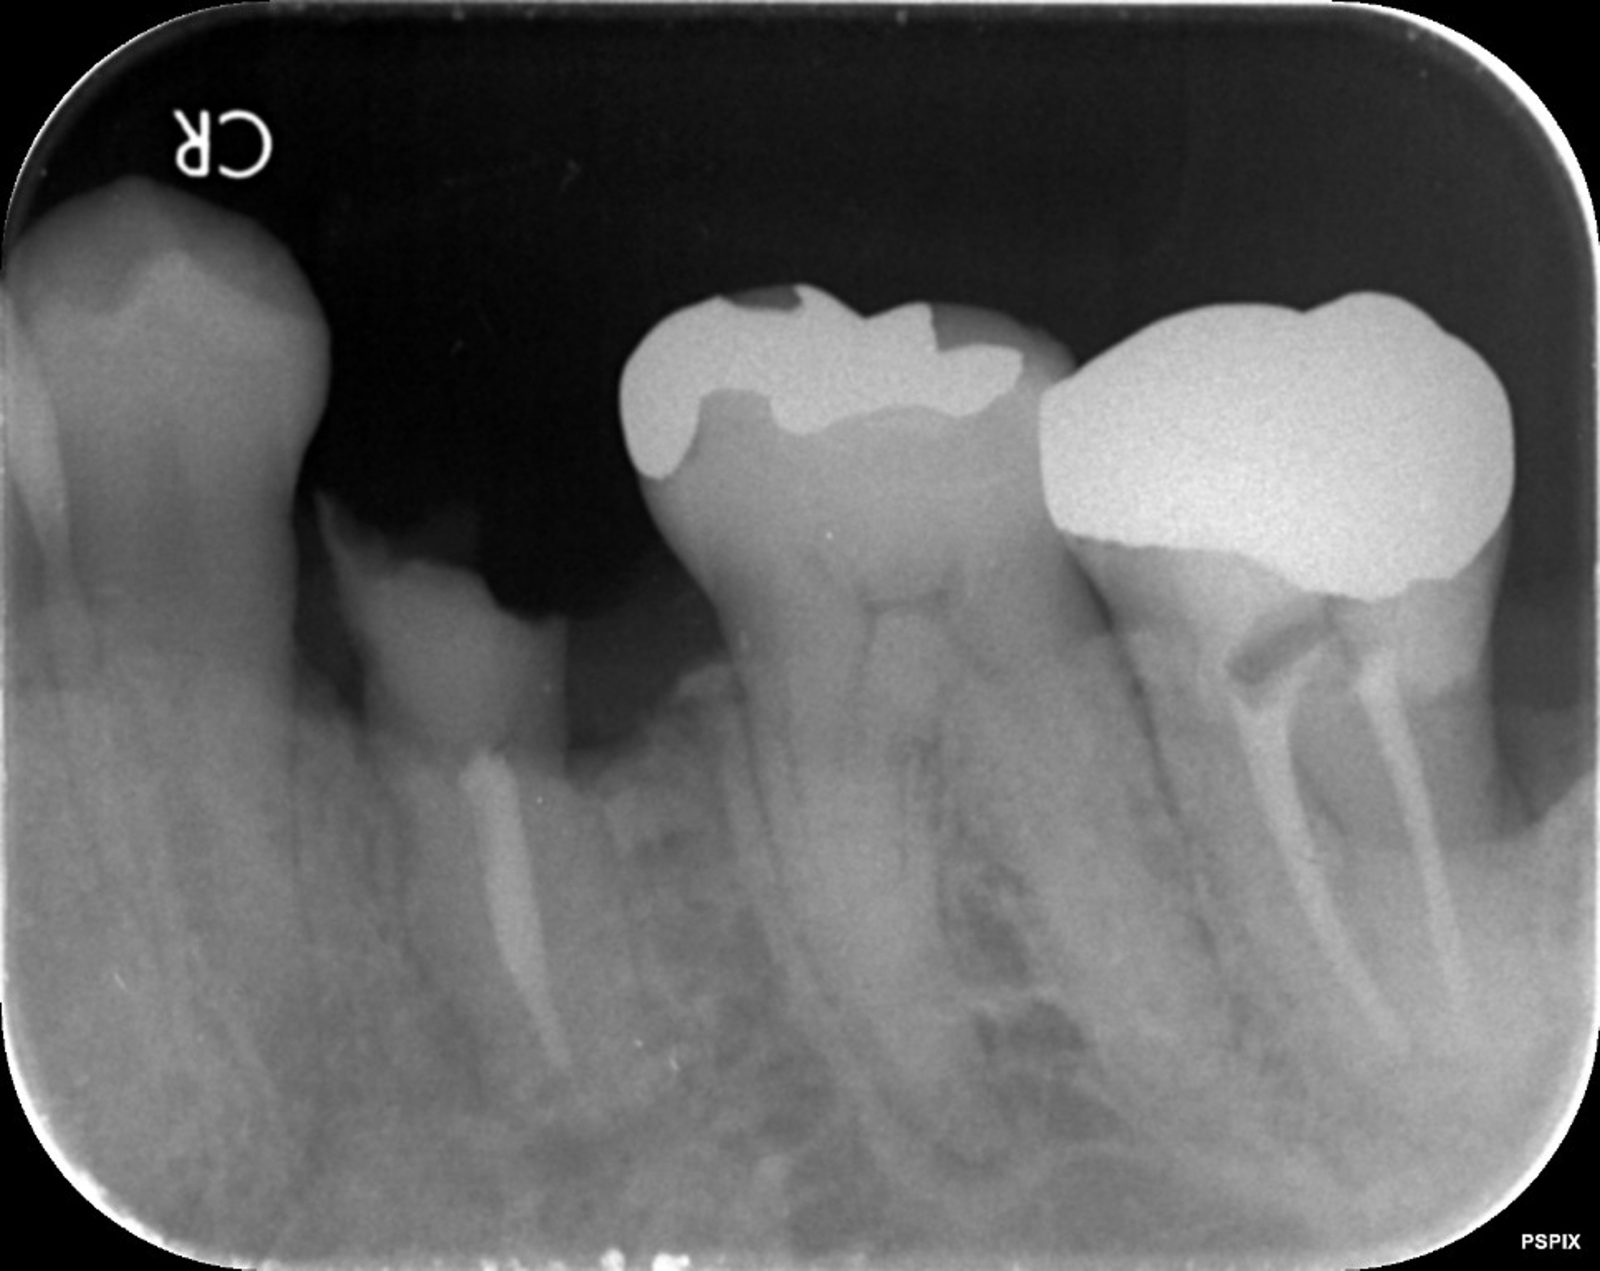

右の写真のように、虫歯が進行して崩壊してしまった歯は、多くの場合に抜歯と診断されます。ここまで崩壊してしまった歯には、被せ物を装着する場所が残っていないためです。

しかし、このような状態であっても「エクストリュージョン法」を活用することで、残せる歯も出てきます。エクストリュージョン法は矯正治療の一種で、残された歯の根を歯茎の外側に引っ張りだし、被せ物を取り付ける場所を作る治療法です。